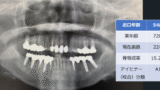

「エックス線歯科健診」の特徴

・体の健診・人間ドックの一部として、顎のエックス線画像を撮影します(約15秒)。

・1枚のエックス線画像から、歯周病、虫歯、歯の本数、根の病気、親知らずの周囲炎、インプラントの周囲炎、顎骨嚢胞等の疾患が検査できます。

・視診では確認できない骨の病変や歯の病気の早期発見も期待できます。

・歯の数と番号を自動認識するAI技術も使用し、歯科医師が確認して所見を記載します。